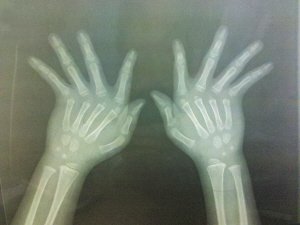

患者的风吹手。

伸出手来,两手的手指都朝小指方向倾斜,犹如无形的大风从中吹过,“吹歪”了手。近日,武汉协和医院接诊了一名罕见的“风吹手”男孩,他的妈妈和外公也有同样的困扰。

冬冬(化名)今年5岁,来自河南。一岁开始抽条,小胖手变“瘦”下来后,父母发现,冬冬的双手有点奇怪,除了大拇指外,其他手指都往小拇指的方向倾斜。

越大,冬冬的手指歪斜越明显,将手指伸直时,中途会有停顿,听到“卡”一声才会被弹直。日常生活能自理,但担心上学后会被歧视,父母带着冬冬到武汉来求医。

协和医院手外科主任陈振兵说,检查结果表示,冬冬手指的肌肉、韧带、关节囊发育不良,导致关节松弛后倾斜,在医学上有个形象的名字,叫“风吹手样畸形”。虽不影响生活,但手指倾斜后,受力不均衡,可能磨损手指肌腱、韧带,或造成肌腱滑脱。

“风吹手”多与染色体遗传基因病变有关,是少见而复杂的畸形。患此病者,通常颅面、脚也可能有相应畸形,冬冬的嘴巴比常人更小,其实是小口畸形,正是病症之一。